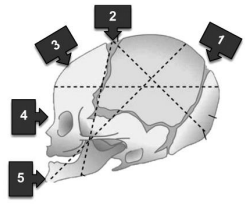

Considere a figura abaixo:

Qual o número que mostra o ponto de referência fetal na apresentação cefálica em que o parto por via vaginal sempre será pouco exitoso?